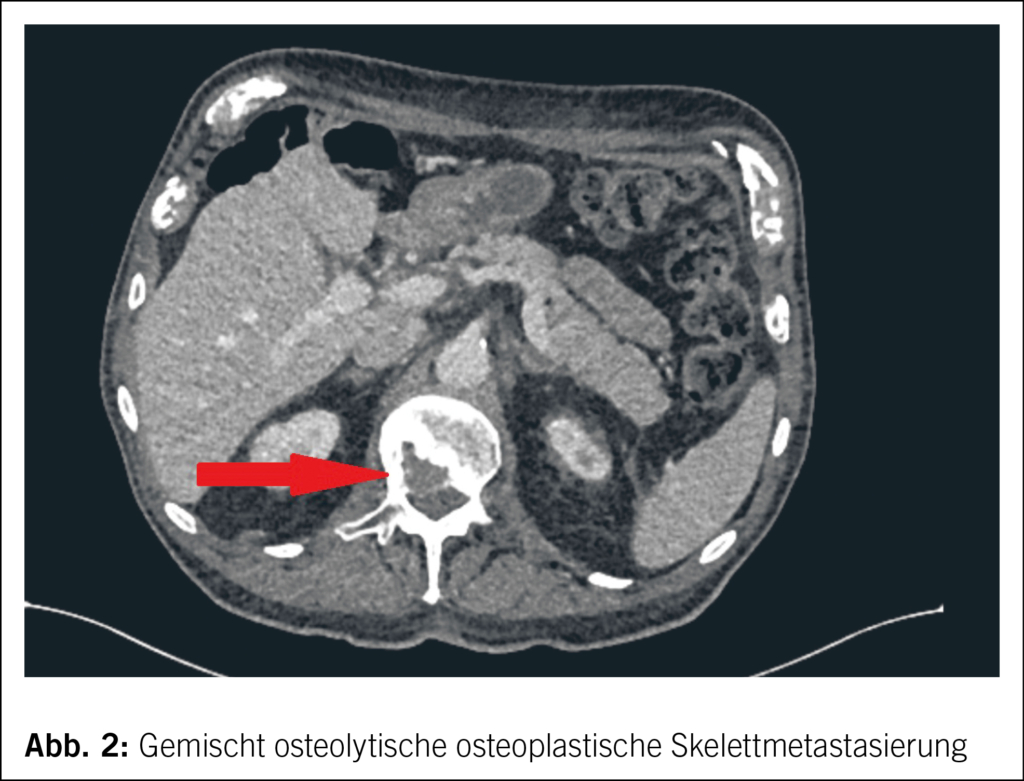

Vor 3 Monaten wurde die Neudiagnose eines ossär metastasierten high-grade Urothelkarzinoms des Pyelons links gestellt (Abb. 2). Die Behandlung dieser Erkrankung erfolgt in der Schweiz. Eine palliative Systemtherapie mit Carboplatin/Gemcitabine wurde eingeleitet.

Zudem erfolgte eine palliative Radiotherapie der ossären Metastasen in der LWS und im Beckenbereich. Unter dieser tumorspezifischen Therapie entwickelte der Patient eine schwere Hämatotoxizität mit nachgewiesener Panzytopenie. Im Rahmen dieser vorübergehenden Immunsuppression kam es trotz vierfacher Impfung gegen SARS-CoV-2 und einmalig stattgehabter SARS-CoV-2-Infektion drei Wochen vor der aktuellen Hospitalisation zu einer Reinfektion. Klinisch zeigte sich ein milder Verlauf, trotzdem wurde in Anbetracht der Tumorerkrankung eine fünftägige Behandlung mit Paxlovid eingeleitet. Danach kam es zu einer raschen Erholung, sodass wir nicht davon ausgehen, dass es sich damals bereits um eine Listerien-Infektion gehandelt hat. Weiter zeigte sich bei bereits bekannter Refluxösophagitis in einer Kontrollgastroskopie ein CMV-positives Magenulkus, welches adäquat mit Valganciclovir behandelt wurde. Nach vollständiger Erholung und laboranalytischer Regredienz der Neutropenie konnte die Chemotherapie 1 Woche vor Eintritt wiederaufgenommen werden.